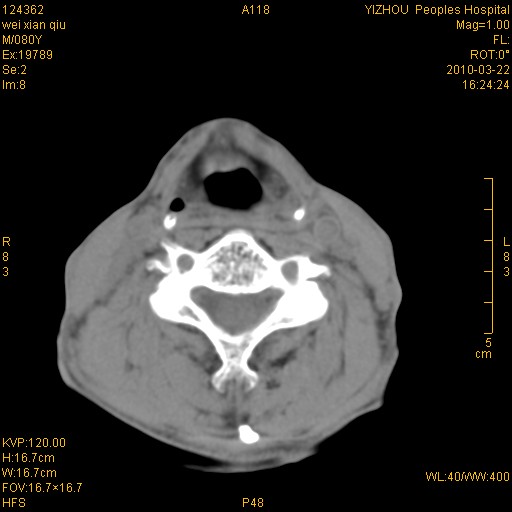

标题: CT25263:喉部占位?

男,80岁.声嘶三月余.

喉前庭右侧壁明显增厚,并见向内突出的软组织密度新生物,表面光滑,其后方软组织层次尚清晰,多考虑:喉部乳头状瘤!建议喉镜并病检!